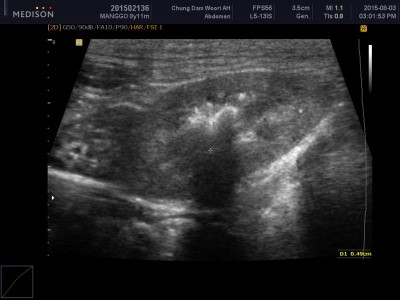

방광 초음파상에도 여러 결석이 확인.

방광 초음파 보면서 복부 초음파도 같이 진행했는데

담낭내 슬러지 확인되었고,

우측 신장내에도 결석 음영이 확인됐습니다.